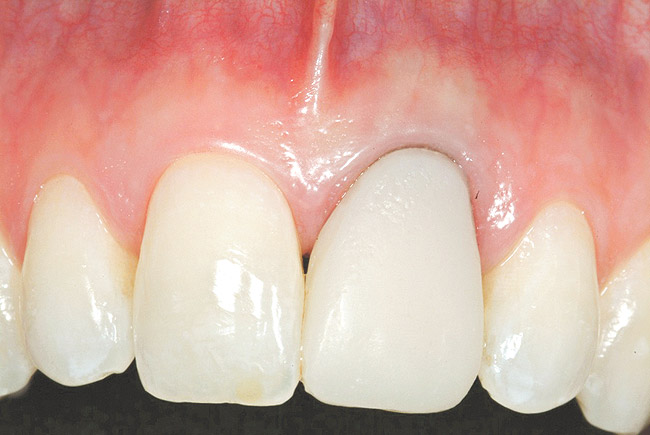

Figure 29  Case Three 3-month postoperative tissue emergence profiles..

Figure 29

The provisional restoration was an immediate non-functional restoration, and was free of contact in centric occlusion, protrusive, and right and left lateral excursive movements. Figure 29 is the 6-week postoperative view. Note the free gingival margin at the mid-facial point of the left central incisor, and compare that to the pretreatment level seen in Figure 21. The site would be allowed to heal and mature for an additional 6 weeks prior to completion of the final implant-supported restoration.